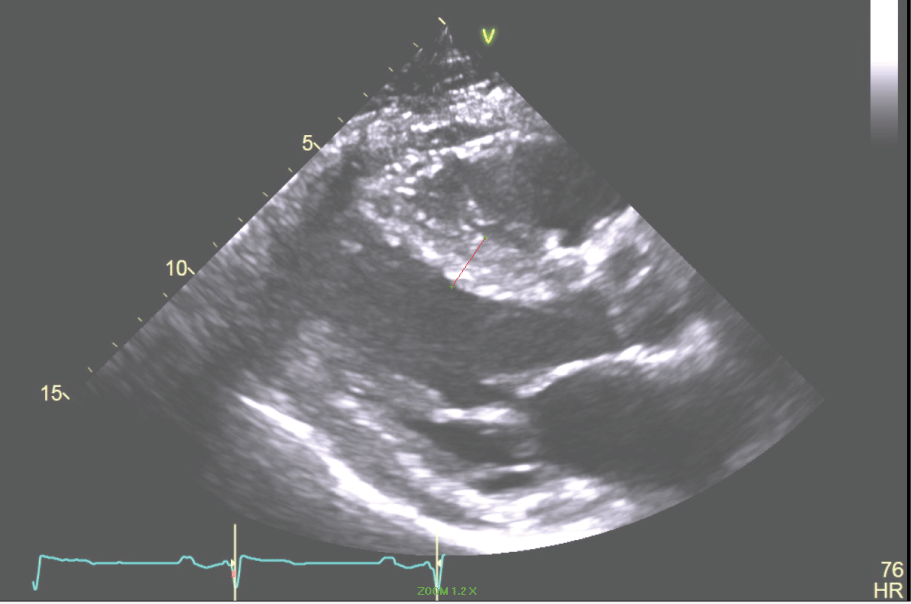

Past Medical History: The patient has a history of gene-negative hypertrophic cardiomyopathy (HCM). In 1983 at age 16 years he had a syncopal episode while playing basketball and was identified to have HCM by echocardiography (Figure 5, Figure 6, Figure 7 and Figure 8). In 2002 the patient had another syncopal episode was found to have non-sustained ventricular tachycardia on Holter monitoring. He had an ICD placed. He had hypertension, coronary artery disease, HCM, hyperlipidemia, syncope, NSVT and post-myocardial infarction VT that was managed with shock therapy.

Figure 5: The Parasternal Long axis of the LV revealing a 17 mm septum in a patient with HCM. View Figure 5